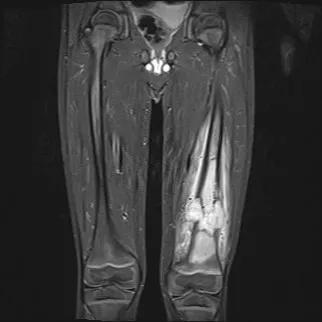

PET scan after CAR T-cell therapy

December 5, 2025/Cancer/Blood Cancers

Case Study: Overcoming Communication Barriers to Enroll Patient in CAR T-Cell Therapy Clinical Trial

Patient achieves complete remission from aggressive marginal zone lymphoma with liso-cel